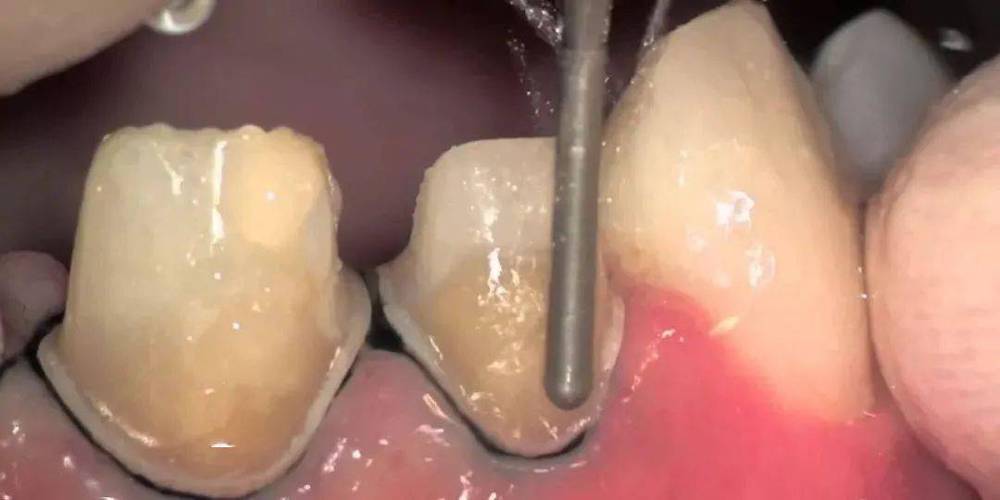

保护牙龈:预备前用排龈线(肾上腺素浓度≤1:10000)排龈5-10分钟,暴露牙颈部边缘;操作时避免车针接触牙龈,减少创伤;术后用冰敷减轻水肿,必要时含漱氯己定漱口水。

边缘质量控制:预备后用牙周探针检查肩台连续性,无粗糙、悬突或中断;取模前用硅橡胶或聚醚材料精确复制肩台形态,避免印模变形导致边缘适合性差。